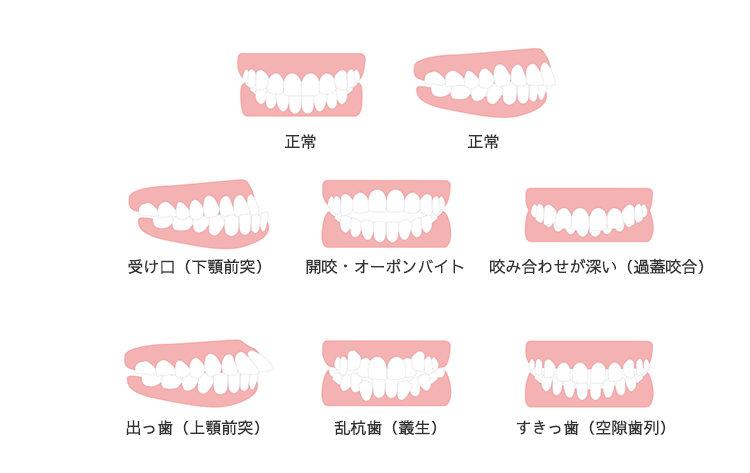

歯並びが原因で思いっきり笑えないなどのお悩みはございませんか?整った歯並びは見た目だけではなく、お口周りへの負担が減り、歯磨きなどのケアがしやすくなるためむし歯や歯周病の予防にも貢献します。

矯正治療には年齢制限はありませんので、お子さんの歯並びから大人の歯並びまでお気軽にご相談ください。

横スクロールができます →

正しい歯並びは全身の健康に繋がります。お口元が気になる方はぜひお気軽にご相談ください。